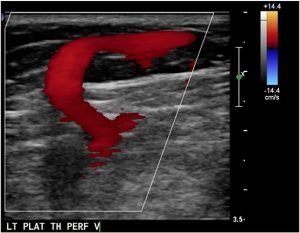

E — Портняжная и подпортняжная вена.

- Входит в фасцию в верхней части колена.

- Наряду с атипичными варикозными венами в бедре наблюдается извилистая рефлюксирующая вена, проходящая внутри портняжной мышцы.

- Требуется диффенциальная диагностика с экстратрункулярными мальформациями.